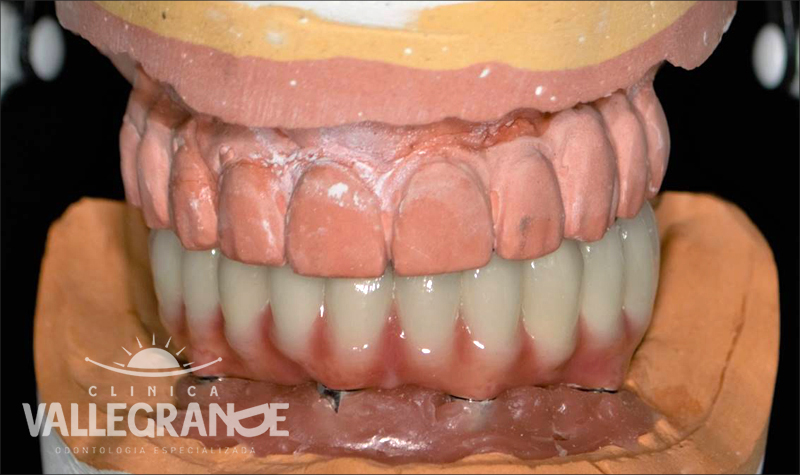

Caso planificado con prótesis híbrida fija completa sobre 4 implantes mandibulares.